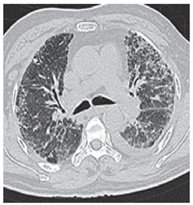

Figure 1: HRCT Shows bilateral diffuse extensive fibrosis with septal thickening, honeycombing, traction bronchiectasis predominantly involving bilateral lower lobs in sub pleural region and architectural distortion resulting in reduced lung volume. Findings are in favour of usual interstitial pneumonia/idiopathic pulmonary fibrosis.